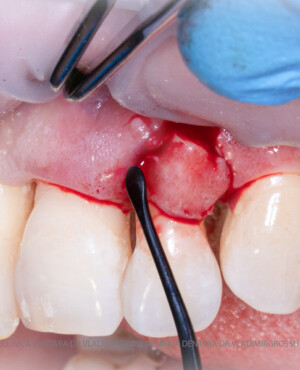

Adiția de gingie (gingivoplastia)

Aditia gingivală este o procedură chirurgicală ce corectează diverse probleme estetice și funcționale, cum ar fi recesiunea gingivală. În implantologia modernă, aditia de țesut moale este utilizată aproape în fiecare intervenție de inserție a implantului dentar pentru a asigura un aspect estetic natural și o bună integrare a implantului în cavitatea bucală.